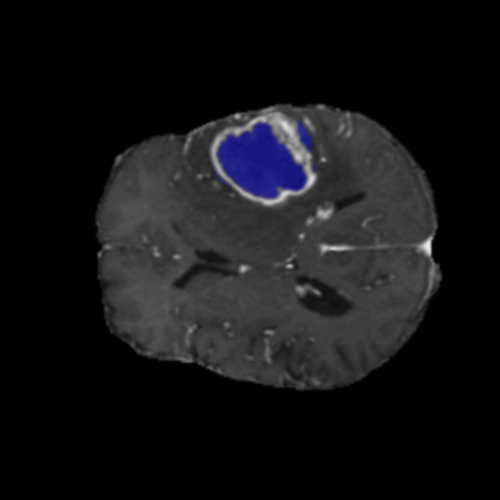

Ejemplos de Modalidades MRI

Visualización de las 4 modalidades de resonancia magnética y las segmentaciones de zonas tumorales utilizadas para entrenar el modelo

Glioma de Alto Grado (HGG)

Núcleo HGG

Núcleo

Edema HGG

Edema

Realce HGG

Realce

Tumor Completo HGG

Tumor Completo

Núcleo Edema Realce

🎯 Zonas Tumorales Segmentadas

• Núcleo (NCR): Región central no viable y necrótica del tumor

• Edema (ED): Inflamación (acumulación de líquido) en tejido cerebral sano circundante

• Realce (ET): Parte activa y viable del tumor, identificada por captación del contraste en T1ce